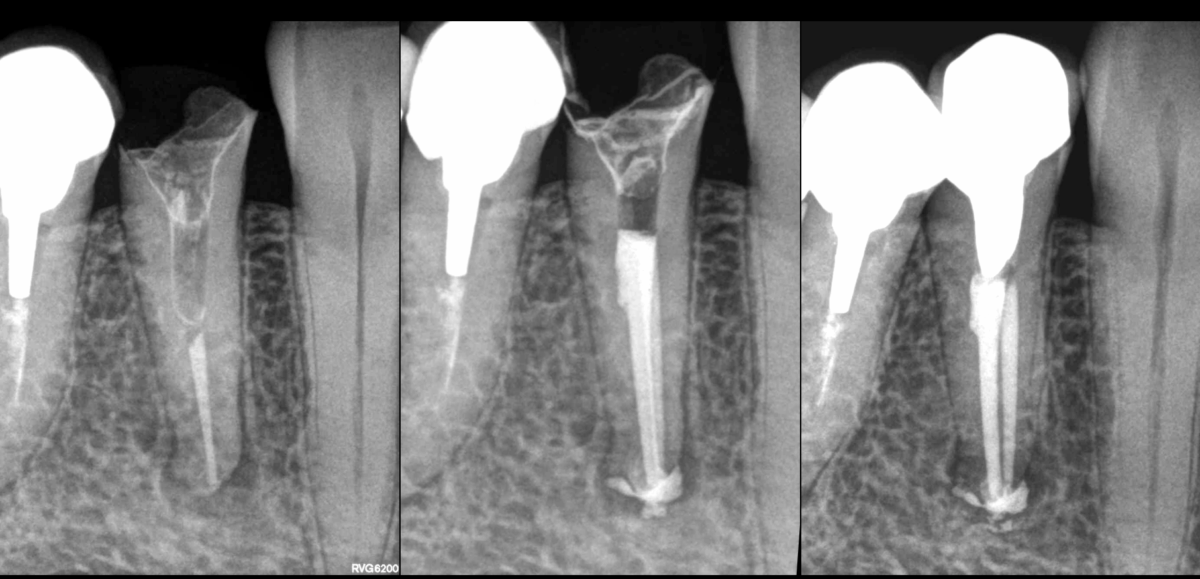

🔍 Dent 44 adressée pour inefficacité du traitement canalaire du point de vue l’environnement osseux.

2️⃣ Parce que le canal présentait une forme particulièrement ovale

👉 𝐏𝐨𝐬𝐬𝐢𝐛𝐥𝐞, 𝐦𝐚𝐢𝐬 𝐩𝐚𝐬 𝐥𝐚 𝐬𝐞𝐮𝐥𝐞 𝐫𝐚𝐢𝐬𝐨𝐧

3️⃣ Parce qu’un canal n’avait pas été traité

👉 ✅ 𝐎𝐮𝐢 : 𝐥𝐞 𝐜𝐚𝐧𝐚𝐥 𝐋.